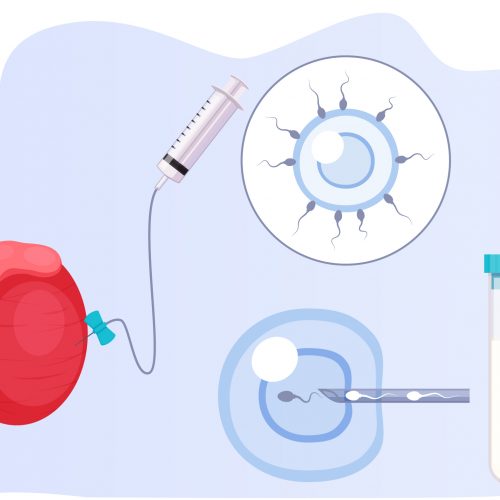

TESA/ TESE/ Mikro-TESE

Erkeklerde azospermiye neden olan bazı durumlarda cerrahi uygulanarak sorun çözülebilir. Örneğin üreme kanallarının tıkanıklıklarında ya da büyük varikosel durumlarında bu sorunların giderilmesi üremeyi sağlayabilir. Ancak günümüzde bu tür cerrahi girişimler yerine daha çok testisten sperm elde edilmesi yöntemlerinin uygulanması tercih edilmektedir. Eğer bir erkeğin semen örneğinde hiç sperm yoksa (azoospermi) bu durumda doğrudan doğruya mikroenjeksiyon...